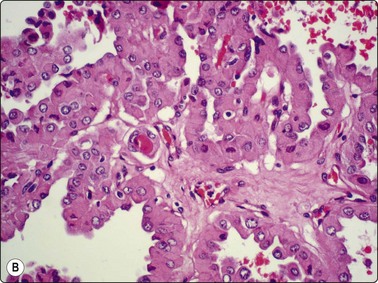

image image image

Fig. 6.28 Poorly differentiated carcinoma

(A,B) Smears showing syncytial clusters of crowded small cells with hyperchromatic nuclei (A, MGG, HP; B, Pap, HP); (C) Tissue section, same case. (H&E, IP).

Until recently, thyroid carcinoma with a poorly differentiated insular pattern was considered to be a distinct entity, a thyroglobulin-producing neoplasm, intermediate in aggressiveness between well-differentiated and anaplastic thyroid carcinoma. Reports have appeared documenting cytological features in insular carcinomas such as high cellularity, dispersed and loosely aggregated cells, solid, cohesive trabecular or papillaroid structures, intact insulae, fragile, ill-defined, granular cytoplasm, oval, hyperchromatic nuclei, occasional INCIs and/or grooves.151-155 However, as insular pattern is often admixed with trabecular and solid growth patterns, the more suitable term ‘primordial carcinoma’ was suggested for this entity.156

The current concept of pure poorly differentiated thyroid carcinoma, as per the Turin proposal156 is one that shows a histologically mixed solid/trabecular/insular architecture, absence of conventional nuclear features of PC and the presence of one of the following three features: cells with convoluted (raisin-like) nuclei, a mitotic index of ≥3 mitoses/10 high-power fields and tumor necrosis. Most tumors are immunohistochemically positive for thyroglobulin and thyroid transcription factor 1, and a subset is also positive for p53.157 Ras mutations are common.

Smears in poorly differentiated thyroid carcinomas are hypercellular with single cells as well as cells in solid, trabecular and insular patterns. There is marked crowding of cells and tumor cells show high nuclear cytoplasmic ratios (Fig. 6.28).158